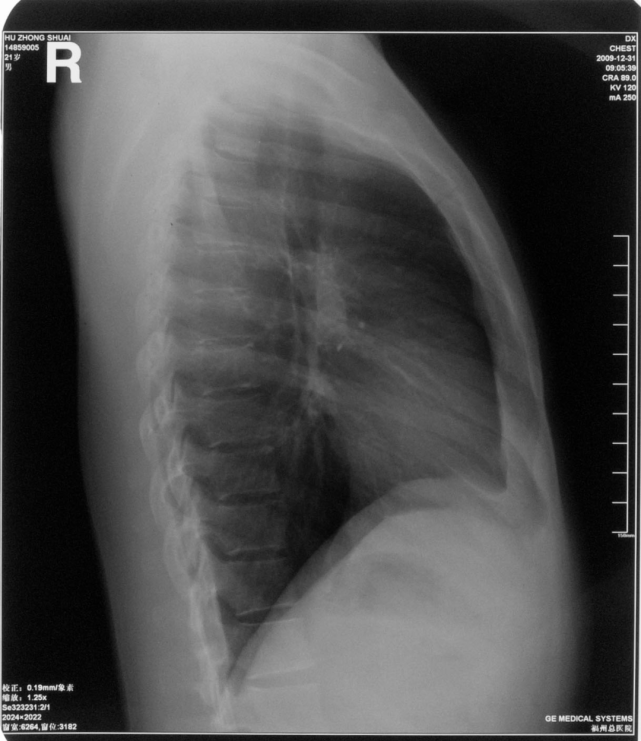

图片

胸部正侧位片

胸部右侧位片